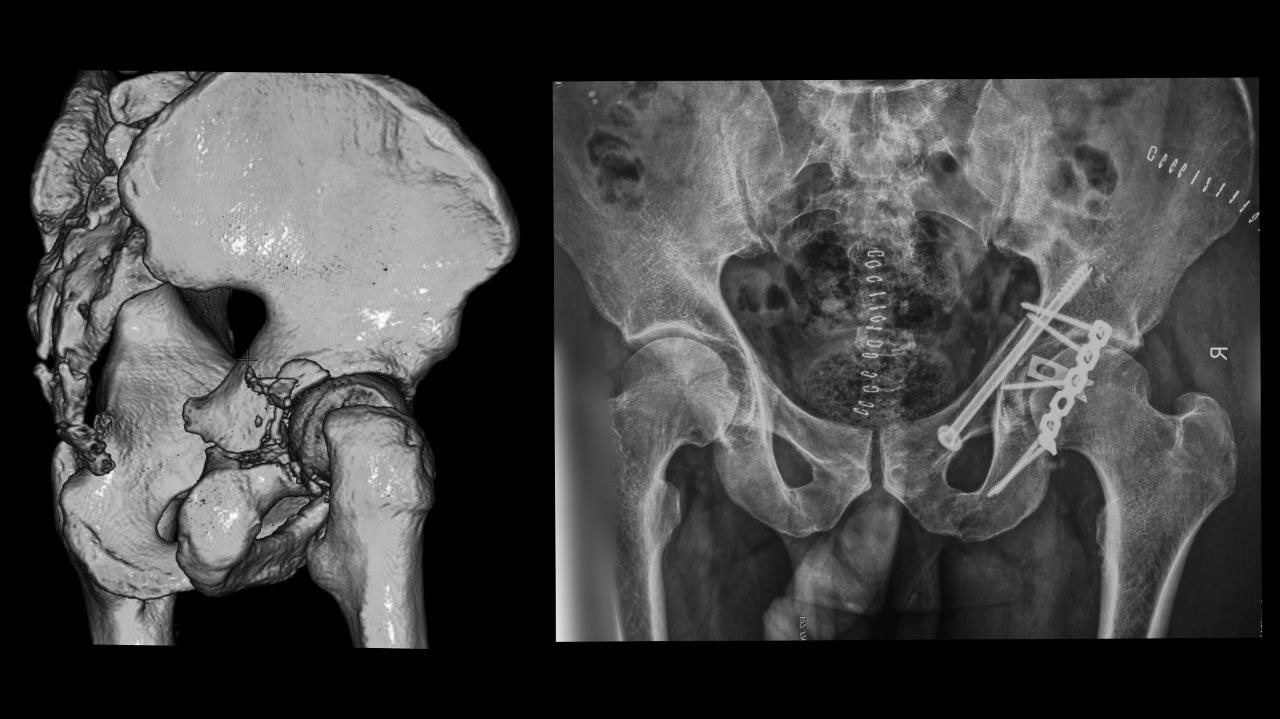

1 three pelv 12.23